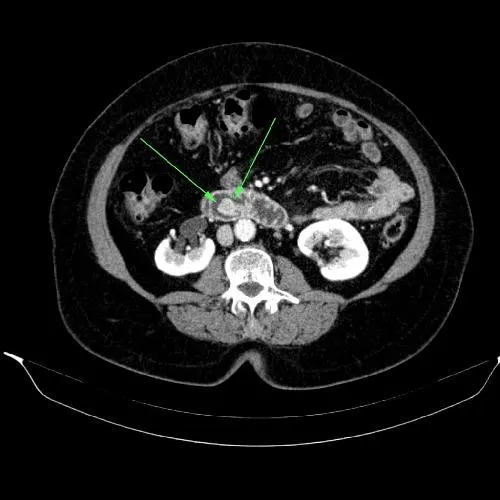

Image Credit: Dr. Bruno Di Muzio, Radiopaedia.org